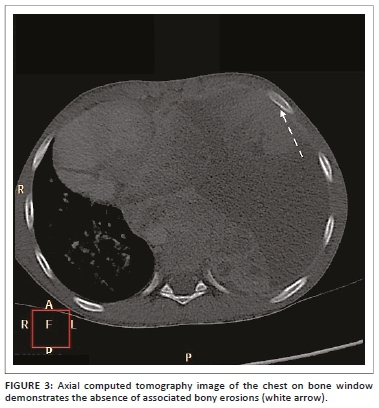

A 7-year-old boy presented with a progressive history of dyspnoea. A chest radiograph (CXR) was performed which demonstrated complete opacification of the left hemithorax with no air bronchograms. This was associated with a cut-off of the left main bronchus and mediastinal shift to the right (Figure 1a and b). An ultrasound (US) showed multiple pleural-based masses with heterogeneous echo texture and an associated complex left pleural effusion. A computed tomography (CT) scan of the chest with intravenous contrast agent demonstrated multiple ill-defined enhancing left pleural-based masses, with patchy hypodense areas (Figure 2a-c). There were no associated intra-tumoural calcifications. These pleural-based masses were locally invasive, as evident by the poor planes of separation between the pericardium (Figure 2a), descending thoracic aorta (which was shifted to the right of the vertebral column), and diaphragm. The findings noted on CXR of the left lung collapse with a cut-off of the left main bronchus and mediastinal shift to the right were also evident. The extra-thoracic extension was also noted anteriorly via the intercostal spaces (Figure 2a). There were no associated erosions of the adjacent ribs (Figure 3) nor extension of the mass into the vertebral canal. A large complex left pleural effusion (25 Hounsfield units [HU]) was also present, as previously noted on the US scan. The right lung and chest wall were normal, with no pulmonary nodules or masses to suggest metastases.

The CT findings depict an ill-defined, large, unilateral, soft-tissue chest wall mass, with heterogeneous enhancement post contrast.2 Low-attenuation regions within the lesion may also be apparent and are representative of haemorrhagic or necrotic areas.2 Associated calcifications are rare, as evident in our case, and have been reported in 10% of the cases.2 Associated rib destruction has been reported in 25% - 63% of the cases.2